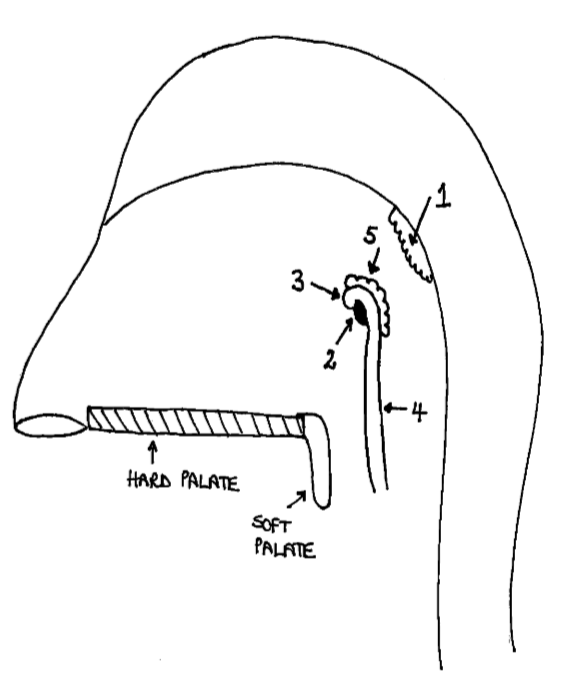

Which area of the head and neck do 1, 2, and 3 make?

pharynx

What region is 1?

nasopharynx

What region is 2?

oropharynx

What region is 3?

laryngopharynx

What is the horizontal dotted line?

pharyngeal isthmus

What is the vertical dotted line?

oropharyngeal isthmus

What is 1?

pharyngeal tonsil

What is 2?

pharyngeal opening of pharyngotympanic tube

What is 3?

tubal elevation

What is 4?

salpingopharyngeal fold

What is 5?

tubal tonsil